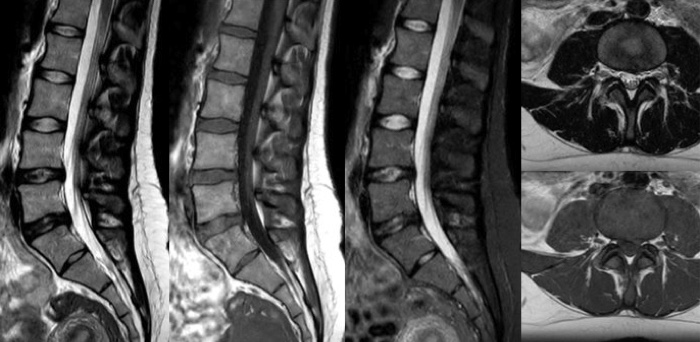

Convierta las imágenes en respuestas hasta un 50% más rápidas

Ponga el tiempo de su lado con Compressed SENSE para reducir el tiempo de exploración hasta en un 50% 2 con una calidad de imagen prácticamente igual. Cree imágenes excepcionales de resonancia magnética con una resolución un 60% más alta para un diagnóstico seguro.

16:30 minutos

Convencional

8:00 minutos

Compressed SENSE

Imágenes de calidad para diagnósticos de calidad

Nuestras bobinas Breeze ultraligeras aportan una versatilidad extraordinaria para obtener imágenes de anatomías complejas y las articulaciones más pequeñas. Además de la excepcional calidad de imagen, ofrece un gran campo de visión de 55 cm y un SNR premium.